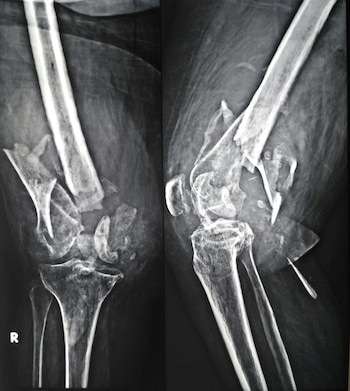

Casos documentados en hospitales y servicios de emergencia confirman que las lesiones más comunes en estos escenarios incluyen: fracturas de fémur, pelvis y tibia, rotura de rótulas, lesiones de columna vertebral y daño severo en articulaciones. Muchas de estas lesiones requieren cirugías múltiples, largos procesos de rehabilitación e incluso pueden dejar discapacidades permanentes.